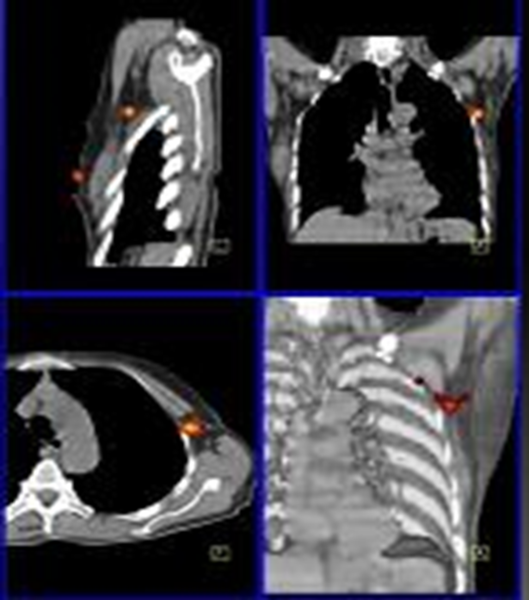

L’indication la plus probante du SPECT/CT en pathologie ostéo-articulaire bénigne est la douleur post-traumatique persistante malgré une radiographie standard négative(1). La technique permet en effet de dépister avec une très grande sensibilité, ou a contrario d’exclure formellement, une lésion osseuse fracturaire, avec ou sans déplacement. Les figures 3a à 3d illustrent parfaitement cette indication dans le cas d’un patient sportif s’étant présenté pour douleurs post-traumatiques et chez qui la radiographie standard se révélait normale, au contraire du SPECT-CT qui mettait en évidence deux fractures, tibiale distale et métatarsienne (fig. 3c et 3d).

Figure 3a à gauche - Radiographies normales suite à un trauma sportif

Figure 3b à droite - Scintigraphie planaire pathologique

Figure 3c -  SPECT/CT révélant une fracture rebord postérieur tibia

Figure 3d - SPECT/CT révélant une fracture base 1er MTT